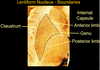

Which structures make up the lentiform nucleus?

Putamen

Globus palidus

What are the three borders of the lentiform nucleus?

Claustrum

Anterior limb

Posterior limb

Which motor axons pass by the Genu of the lentiform nucleus?

Corticobulbar axons

Which axons pass by the posterior boundary of the lentiform nucleus?

Corticospinal axons